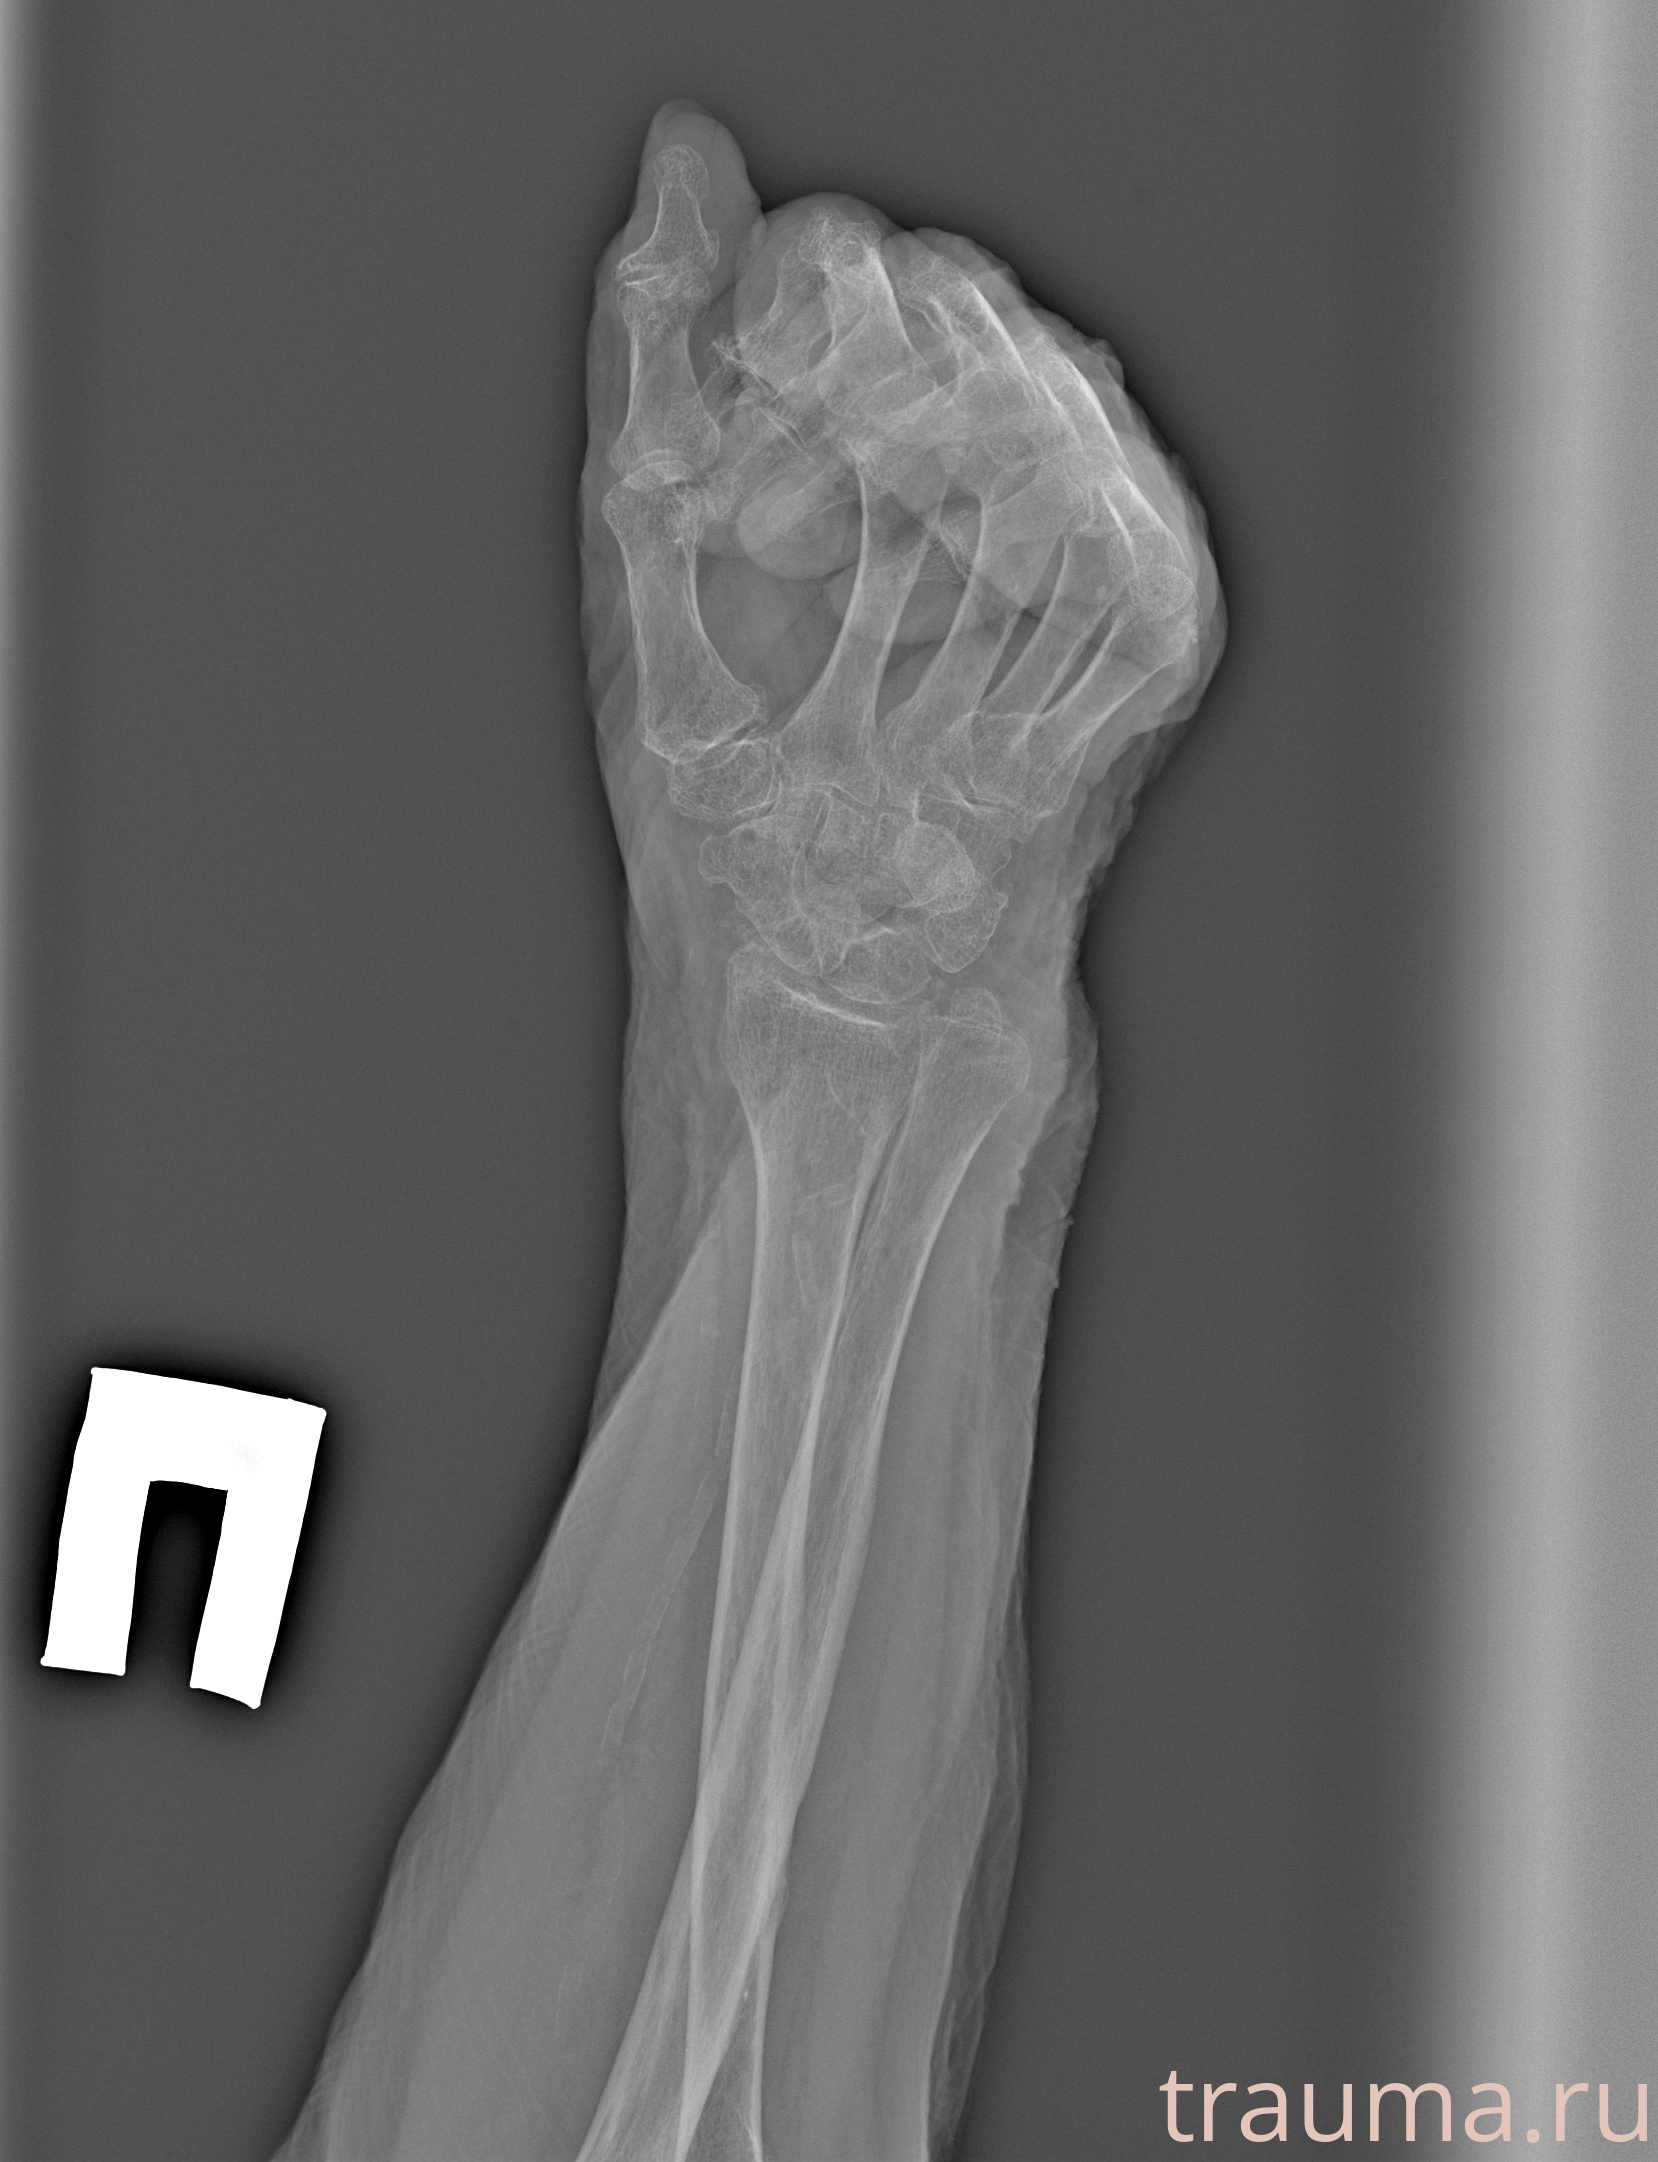

Рентген на дому: по вашему адресу приезжает врач-рентгенолог, травматолог-ортопед с мобильным рентгеновским аппаратом, проводит диагностику травмы или заболевания, делает необходимые рентгенограммы, дает рекомендации по дальнейшему лечению. Получить качественные снимки в домашних условиях возможно благодаря уникальной методике, разработанной МосРентген Центром для института  Склифосовского